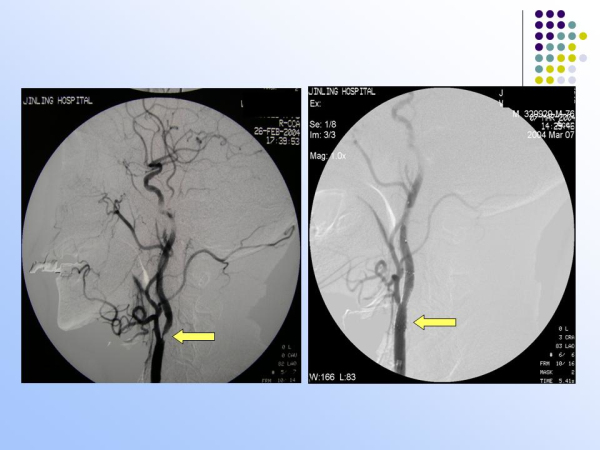

【治疗脑血管病的新技术:血管内介入治疗】—神经内科脑卒中筛查与防治办公室

脑卒中筛查与防治办公室